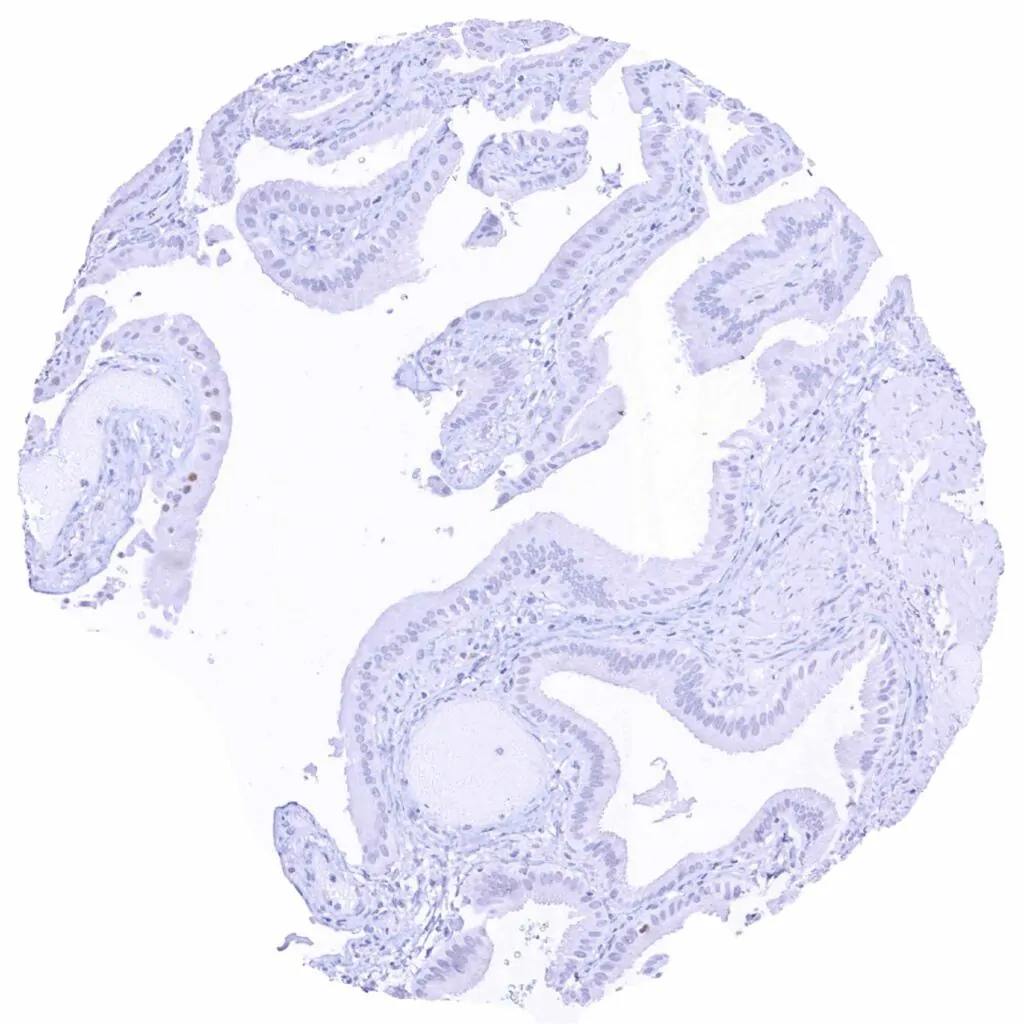

Uterus, endocervix